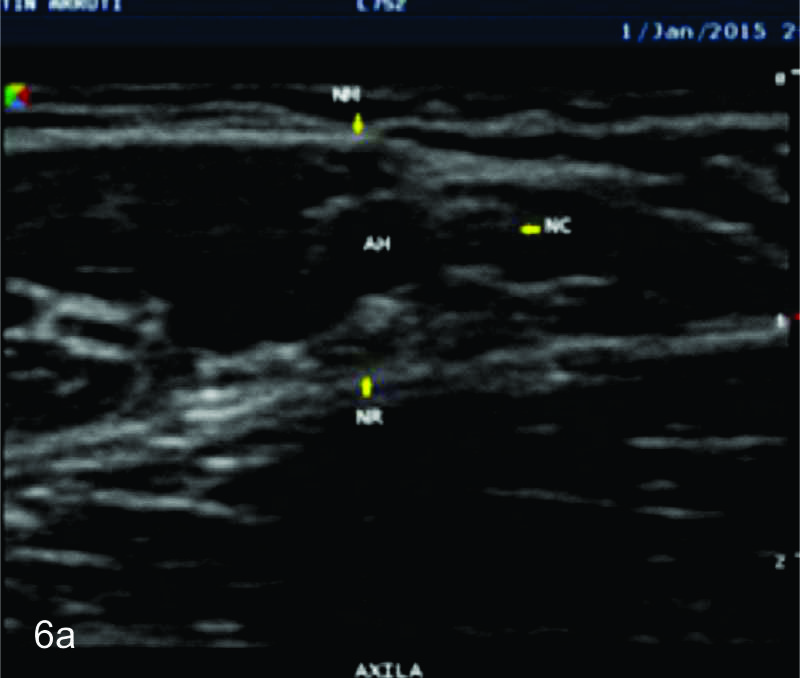

Figura 6

Nervio cubital

Figura 7

Serie de cortes axiales del nervio cubital desde su origen a nivel del hueco axilar hasta su terminación a nivel del canal de Guyon. Se identifica el mismo señalado por flechas amarillas y con las letras NC. AH-arteria humeral, PC- músculo prondador cuadrado, P- hueso pisciforme, Línea roja- ligamento anular del carpo, Línea amarilla- túnel de Guyon, Flecha azul- Arteria cubital-. A-tercio distal antebrazo, B- canal de Guyon.